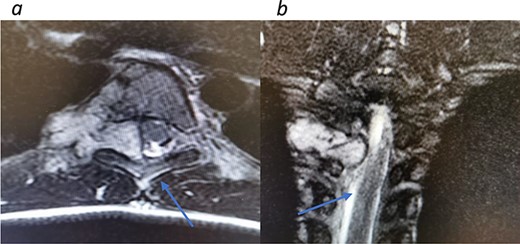

Redemonstrations of tumor post VATS. (a) Axial view tumor noted with arrow causing significant narrowing of the canal. (b) Coronal view of thoracic spine showing involvement of the spinal canal.

Appropriate tests were done (vanillylmandelic acid and norepinephrine metabolites were found to be slightly high, urine metanephrines were within normal limits, insulin-like growth factor-1 (IGF-1), IGF-binding protein, adrenocorticotropic hormone, cortisol and growth hormone levels were all normal. During her clinic follow-up 6 months post resection, a positron emission tomography (PET) scan showed hypermetabolic activity in the soft tissue at the level of T5 and adjacent right costovertebral junction with possible residual tumor and T5 involvement (Fig. 3). Magnetic resonance imaging was carried out after and showed significant narrowing of the spinal canal at the level of T5 and T6 and focal signal intensity at T5 suggestive of bone involvement (Fig. 4).

A diagnosis of recurrent paraspinal paraganglioma was made and she was admitted for tumor resection. Through posterior approach, laminectomy of T5, lower part of T4 and upper part of T6 was done (Fig. 5). The tumor was exposed and resected along with the parietal pleura. Tumor specimen was sent for histopathology, which confirmed the recurrence of the tumor.